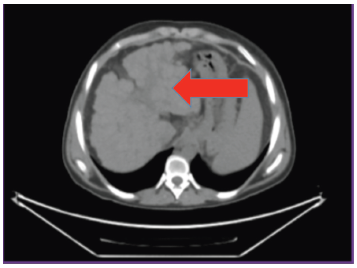

A 1250-g diseased liver was explanted (Figure 2), and the new graft from the left lobe of the patient’s brother (a 500-g living liver graft) was implanted. After completion of vascular anastomoses in the anhepatic phase, reperfusion was initiated after portal vein unclamping. At the end of the 7.5-hour surgery, Doppler ultrasonography confirmed normal flow in the portal vein, hepatic artery, and hepatic veins. The transplanted liver was clearly visualized by computed tomography-angiography (Figure 3).

Figure 3. Liver Computed Tomography-Angiography of Patient, Showing Transplanted Liver